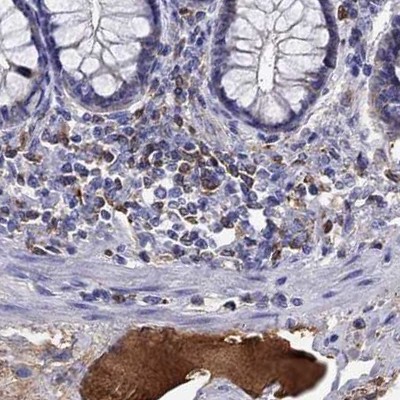

Immunohistochemical staining of human cerebral cortex, cervix, uterine, colon and liver using Anti-SERPINA3 antibody HPA002560 (A) shows similar protein distribution across tissues to independent antibody HPA000893 (B).